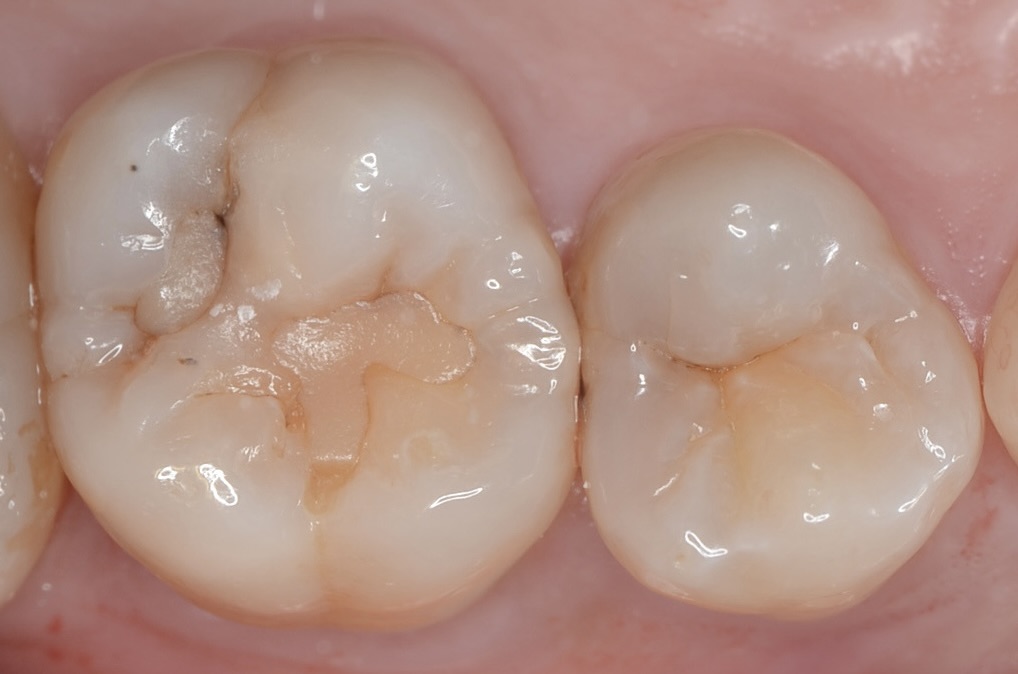

20代 虫歯治療 ダイレクトボンディング #33

Before

After

| 年齢 | 20代 | 治療方法 | ダイレクトボンディング |

|---|---|---|---|

| 性別 | 女性 | 通院回数 | 3回 |

| 主訴 | できるだけ歯を削る量を少なくしてむし歯を治したい | 費用 | 231,000円(税込) |

| 治療のメリット | 歯を削る量を少なくできる・自然な見た目・境目がピッタリできる | ||

| 治療のデメリット | 大きい虫歯治療には適応できない場合がある | ||